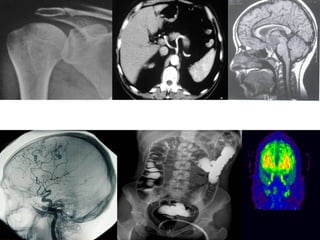

• Radiografia

• Uma radiografia é um filme ou outro material de

base que possui uma imagem processada de uma

determinada região anatômica do paciente

(produzida pela ação dos raios X no filme);

• É a produção de radiografias e/ou outras formas de

imagens radiográficas;